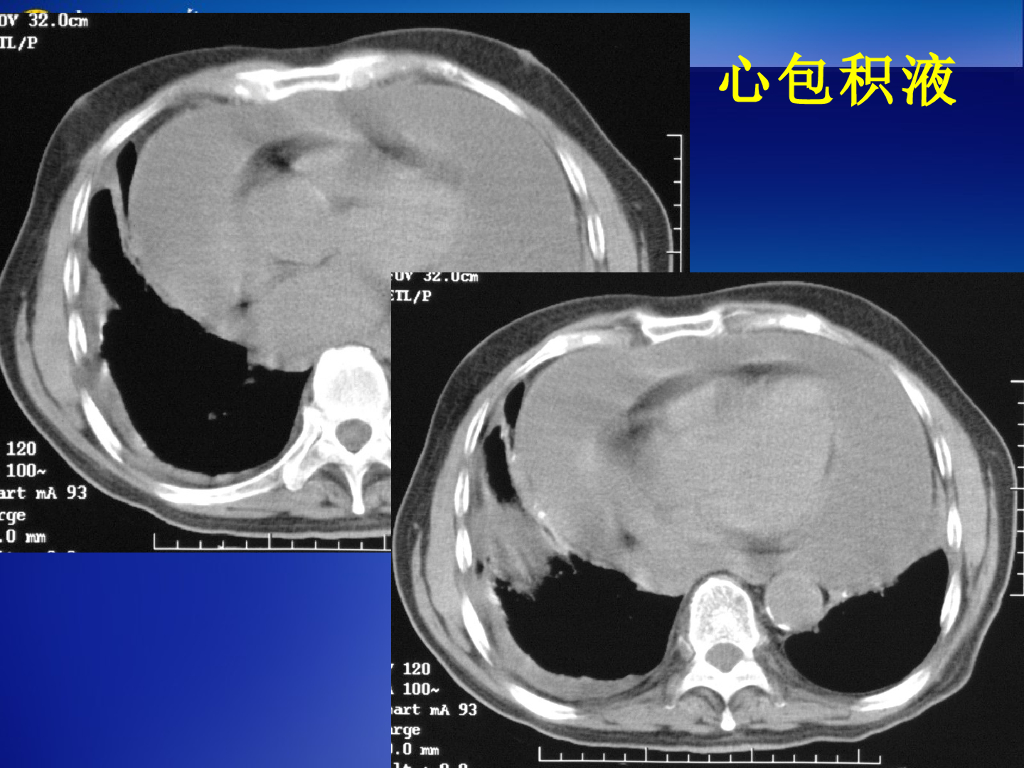

《放射诊断学》演示文稿-心肌、心包病变--实习.pdf